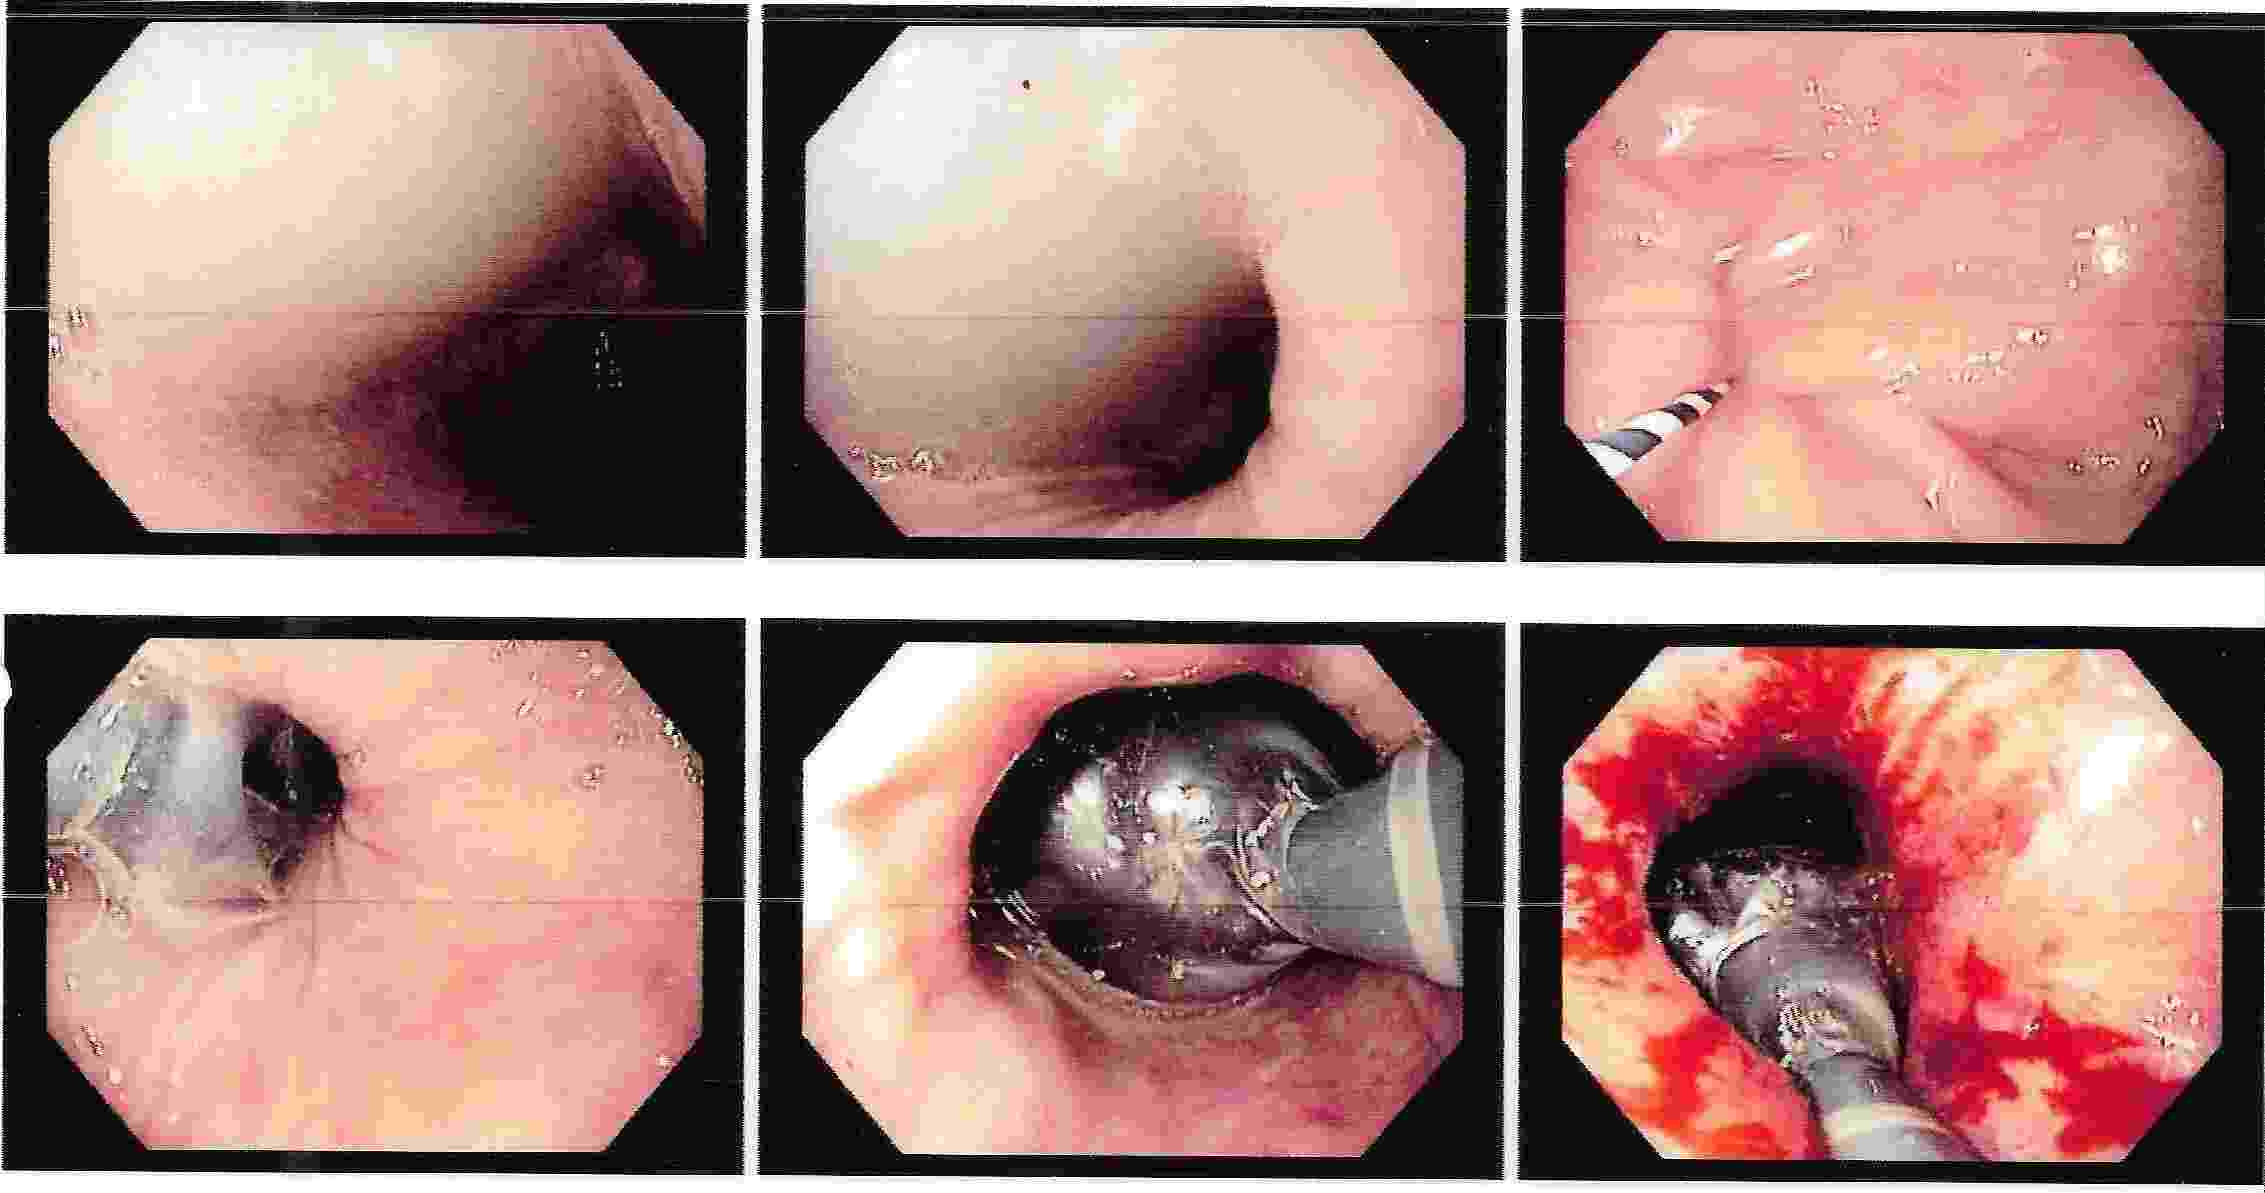

Strong contractions of the food pipe is known as dysmotility of esophagus and an unusual condition known

as Achalasia Cardia due to powerful contraction of the valve of the esophagus at its lower end which

can cause difficulty in swallowing.

Achalasia Cardia - Balloon Dilatation

Achalasia Cardia - Balloon Dilatation

Achalasia Cardia - Balloon Dilatation

Achalasia Cardia - Balloon Dilatation